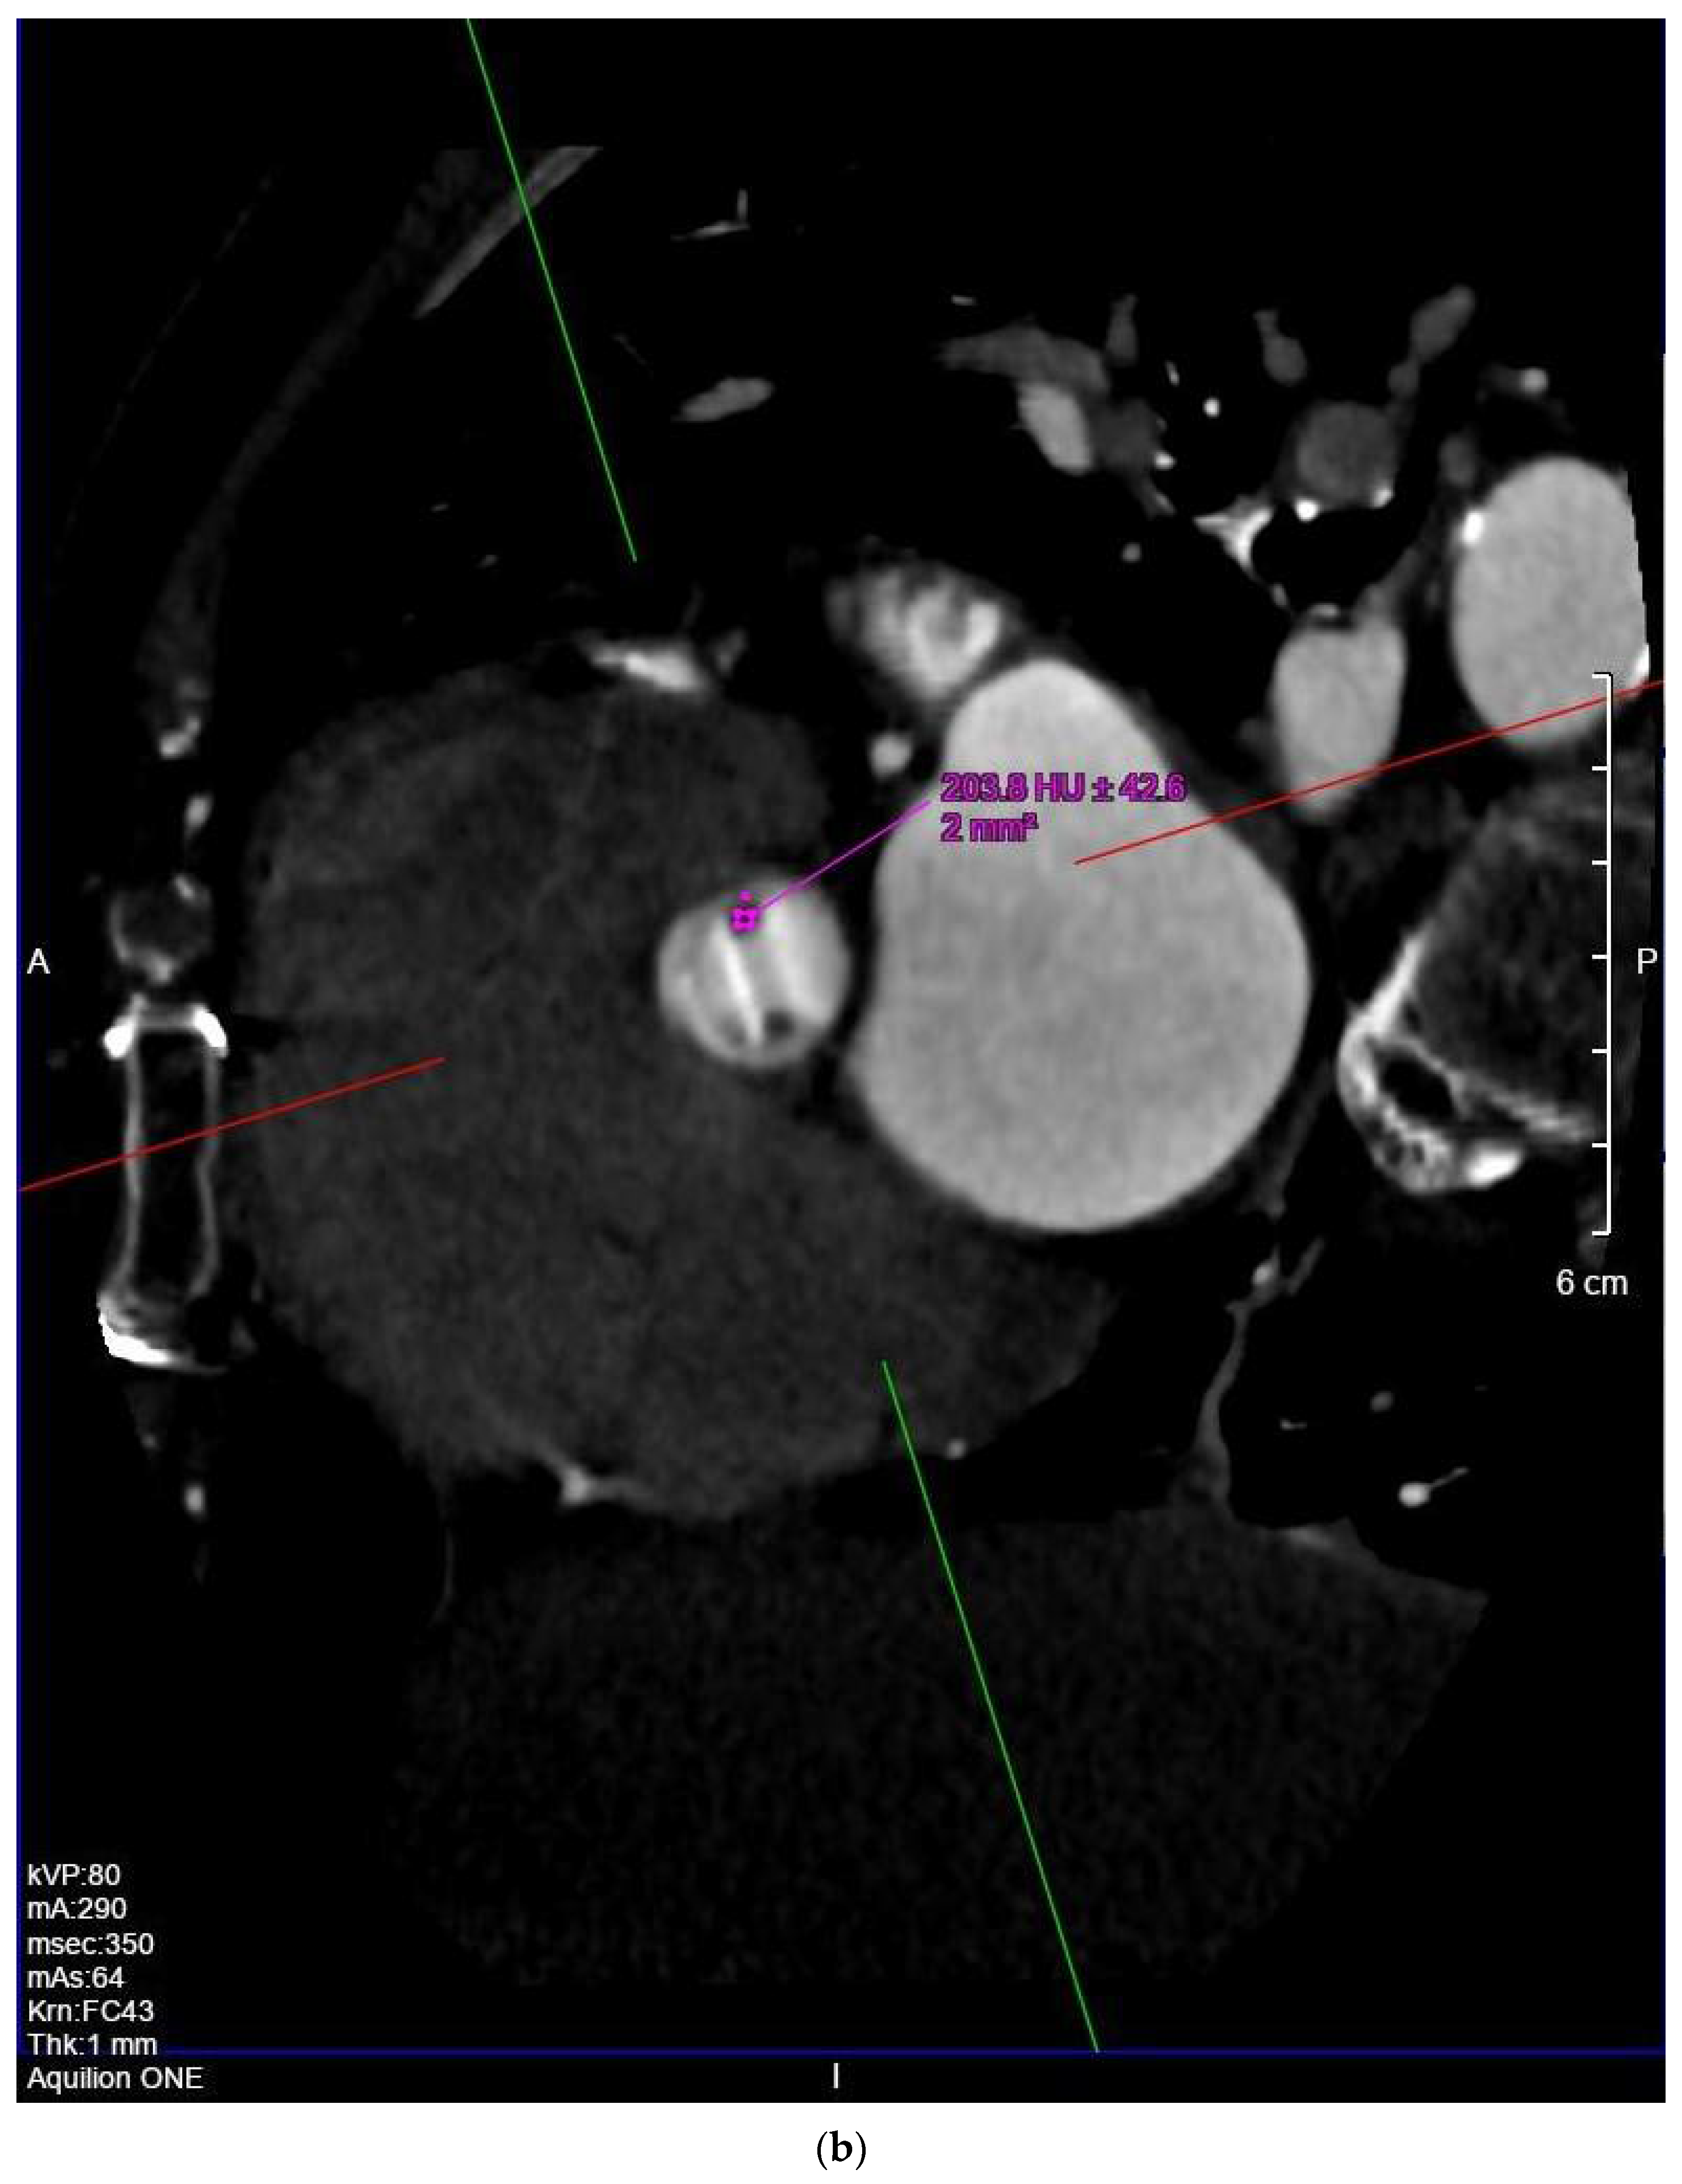

2.2. Case 2